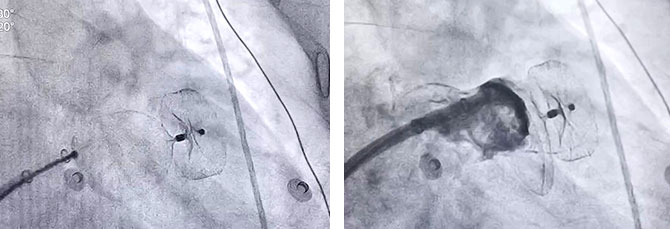

三例患者手术主刀的分别是三位心血管内科邓海、方咸宏、董豪坚3位主任。心血管内科团队成功精准定位左心耳封堵器固定盘,在DSA下牵拉封堵盘,固定盘稳定未发生相对位移。左心耳封堵器释放位置良好、固定盘及封堵盘稳定、无残余分流、对周围组织无影响,呈经典“轮胎状”,符合PAST释放标准原则,释放封堵器,完美封堵。

牵拉实验稳定,固定盘未发生相对位移 封堵完全,无残余分流